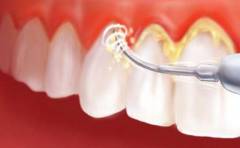

- Удаление зубных отложений с помощью специальных инструментов. Это первый этап лечения, без которого эффективность терапии будет низкой.

- Удаление зубных отложений с помощью специализированных инструментов (крючки, экскаваторы, ультразвук). Это важный этап, без которого эффективность терапии низкая и высок риск рецидивов. После удаления отложений десны обрабатываются антисептиками.